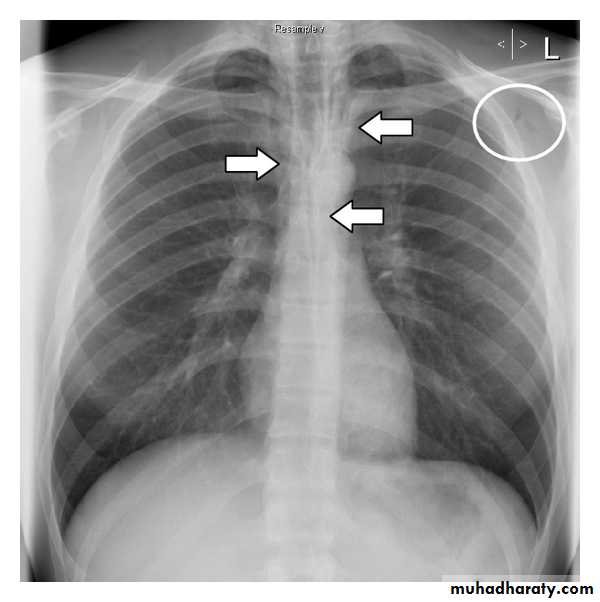

Right upper lobe collapse has distinctive features, and is usually easily identified on frontal chest radiographs .

Radiographic features

Chest radiograph

Collapse of the right upper lobe is usually relatively easy to identify on frontal radiographs. Features consist of :

increased density in the upper medial aspect of the right hemithorax

elevation of the horizontal fissure

loss of the normal right medial cardiomediastinal contour

elevation of the right hilum

hyperinflation of the right middle and lower lobe result in increased translucency of the mid and lower parts of the right lung

right juxtaphrenic peak

A common cause of lobar collapse is a hilar mass. When a right hilar mass is combined with collapse of the right upper lobe, the result is an S shape to elevated horizontal fissure. This is known as Golden S sign .

Non-specific signs indicating right sided atelectasis are also usually present including:

elevation of the hemidiaphragm

crowding of the right sided ribs

shift of the mediastinum and trachea to the right